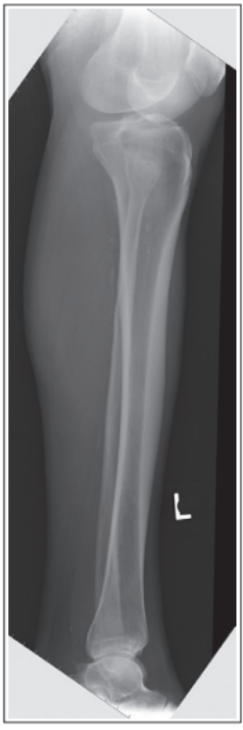

Proximal tib/fib are not superimposed

Over superimposition of tib/fib

Superimposition of proximal tib/fib

Obliquity is less than 45 degrees, meaning its under-rotated